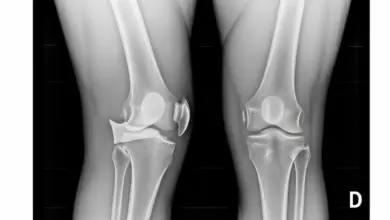

- Radiografias: úteis para descartar fraturas e identificar a fratura de Segond.